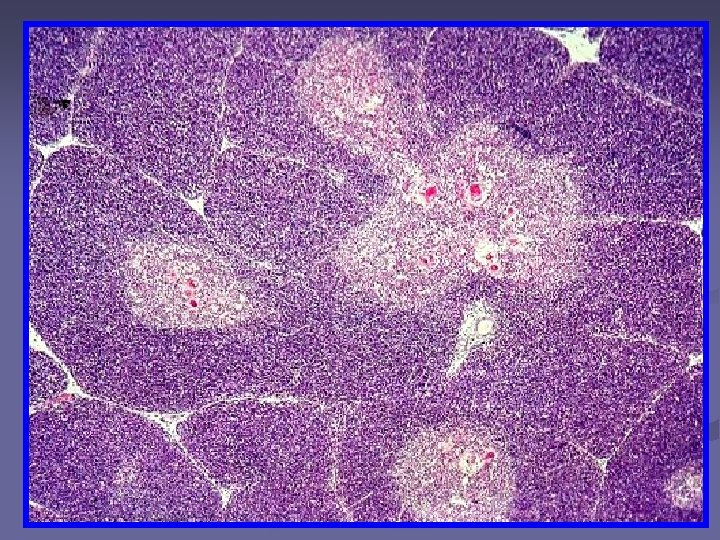

n Pulpa alba Parenchimul - formata din tesut limfoid dens - se organizează in jurul arterelor Rol: procesele imune Pulpa rosie – tesut reticular lax, lacunar, – se organizeaza in jurul sinusurilor venoase. Rol: filtrează sângele Pulpa alba n Pulpa rosie

Splina – col. HE Pulpa alba Pulpa rosie